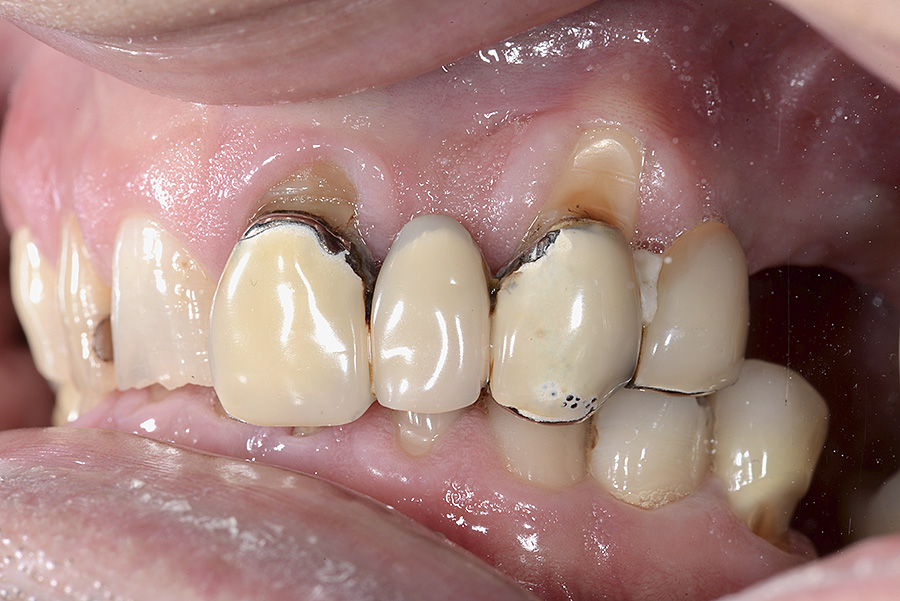

PREMESSA: in seguito all’estrazione dell’incisivo laterale superiore di destra, resasi necessaria per cause batteriche, si decide di affrontare il caso con il posizionamento di un impianto in sostituzione dell’elemento mancante dopo guarigione del sito infetto. Con tecniche rigenerative sia dei tessuti ossei mancanti a causa dell’infezione pregressa, sia dei tessuti gengivali che appaiono inizialmente troppo spostati in alto, si ripristina una corretta morfologia delle parabole (contorni) gengivali e delle papille interdentali (triangoli di gengiva tra due denti vicini).

Vengono utilizzati 2 tipi di provvisori: il primo, cementato ai denti vicini, viene utilizzato dal momento dell’estrazione del dente fino ad impianto osteointegrato (circa 6 mesi); il secondo, avvitato direttamente all’impianto, ha una funzione di prova estetica ma soprattutto di guida per la maturazione dei tessuti gengivali peri-implantari portandoli verso la maturazione completa prima di posizionare la corona finale in disilicato di litio.